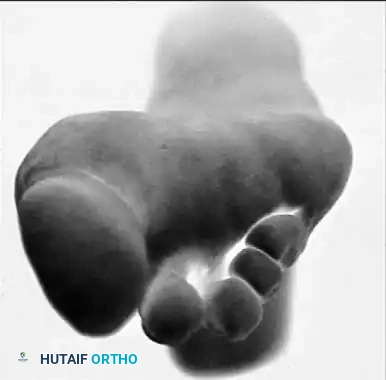

Fig. 81-1 Rheumatoid foot. Note the multiple severe deformities characteristic of rheumatoid arthritis of the forefoot, including advanced hallux valgus, subluxed and dislocated lesser metatarsophalangeal joints, claw toes, hammer toes, and prominent bursal formation.

The hyperextension and eventual dislocation of the MTP joints yield several clinically significant and highly symptomatic deformities:

- Distal Migration of the Plantar Fat Pad: As the proximal phalanx dislocates dorsally, it drags the plantar aponeurosis and the protective plantar fat pad distally.

- Intractable Plantar Keratoses (IPKs): The metatarsal heads are left completely uncovered and prominent against the plantar skin, leading to painful callosities and a high risk of skin ulceration.

- Digital Contractures: Fixed flexion contractures of the PIP and DIP joints (claw toes) and the interphalangeal joint of the hallux develop.

- Dorsal Prominences: Painful hard corns form over the dorsum of the PIP joints, and end corns develop at the nail-pulp junction due to abnormal weight-bearing on the toe tips.

Fig. 81-4 Multiple deformities of rheumatoid arthritis. Note the prominent bursa directly over the medial eminence and the severe dorsal posturing of the lesser digits.

Epidemiological data strongly supports the prevalence of these deformities. Vidigal et al. evaluated 104 patients with RA and noted that 77% exhibited lesser MTP joint subluxation, with 30% developing pressure lesions secondary to hammer toes. Furthermore, hallux valgus deformity was present in 70% of these patients, often accompanied by a varus deformity of the fifth digit.